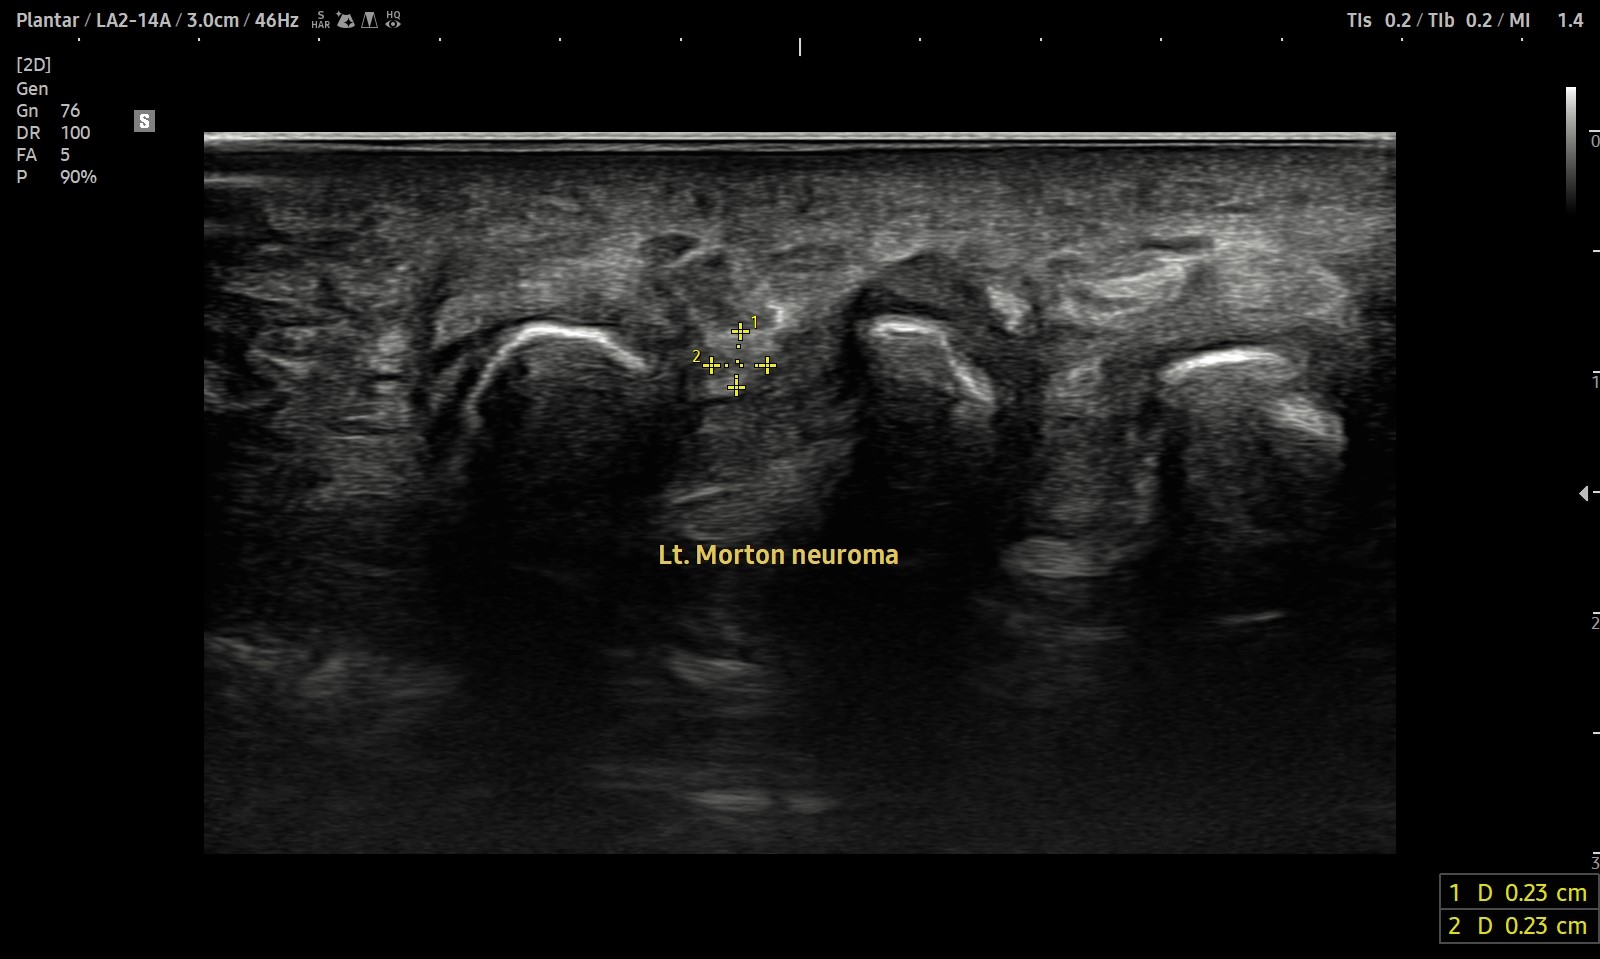

- 치료기간 : 25 . 5 . 3 ~ 25 . 9 . 11

- 치료횟수 : 10 회 (2 cycle)

우측 발 (치료 전 → 후)